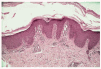

Los estudios analíticos practicados fueron normales (hemograma y bioquímica de sangre y orina). Se realizó una biopsia cutánea a nivel del dorso del pie que mostró hiperplasia psoriasiforme con hiperqueratosis y paraqueratosis focal e hipergranulosis e infiltrado linfocitario perivascular leve en dermis superficial (fig. 3).

Fig. 3.--Hiperplasia psoriasiforme con hiperqueratosis y paraqueratosis focal.

El diagnóstico de PRP se basa en la correlación clínico-histológica. Los hallazgos histológicos son típicos, pero no patognomónicos, variando según el estadio del proceso9. En la epidermis se aprecia acantosis irregular con hiperqueratosis ortoqueratósica, más marcada en los orificios foliculares donde forma tapones córneos. Es característica la presencia de focos de paraqueratosis en torno al orificio folicular, con ocasional espongiosis y degeneración vacuolar de la capa basal, y a diferencia de la psoriasis la granulosa está conservada o aumentada, no existiendo microabscesos de Munro. En la dermis se observa un infiltrado perivascular mononuclear y atrofia de las glándulas sebáceas, siendo normales los folículos pilosos4,8,10.